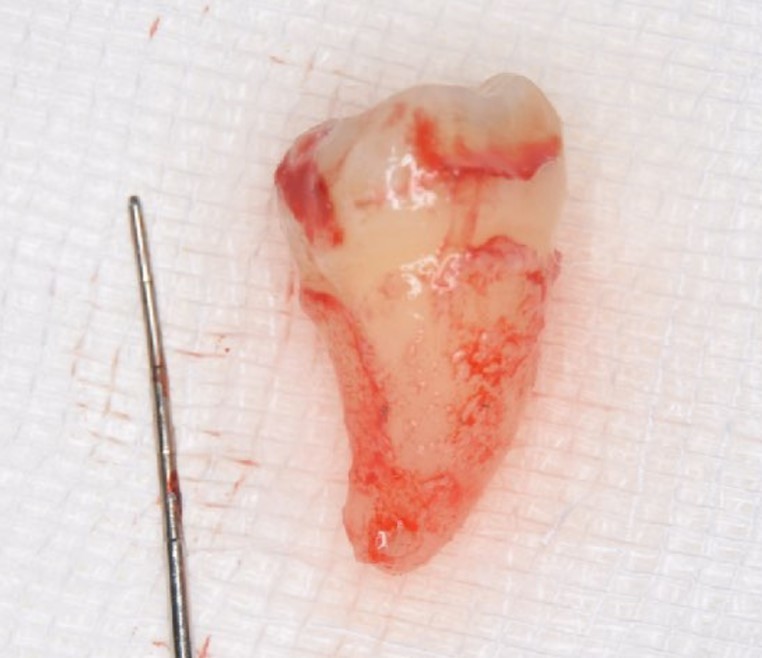

The patient was given amoxicillin/clavulanic acid at 250 mg (Sawacillin Capsules, Japanese Pharmacopoeia, Japan) one hour prior to surgery. Under local anesthesia (GINGICAINE GEL, Hakusui Trading CO., LTD, Tokyo, Japan ), with an inferior alveolar nerve block used for tooth #46 alonb with 2% lidocaine and 1:80000 epinephrine (Dentsply, Tokyo, Japan), that tooth was separated and its fragments were gently extracted with a dental elevator. Granulation tissue was then removed and the socket was prepared with an internal cooling carbide bur. The graft bed was formed using the CT measurements as an index. Abundant rinsing with 0.05% chlorhexidine gluconate and sterile saline (OTSUKA NORMAL SALINE, Otsuka Pharmaceutical Factory, Inc., Tokushima, Japan) was performed to eliminate debris. Tooth #48 was gently extracted with forceps and dental elevators, and meticulously examined, and the absence of fractures was confirmed. Also, the periodontal ligament in the extracted graft tooth was observed and considered to be sufficient, then, after measuring length with a probe, it was stored in saline (Figure 4).

Figure 4.Extraction of #48 was performed without damaging the periodontal ligament. Abundant periodontal ligament tissue could be seen.